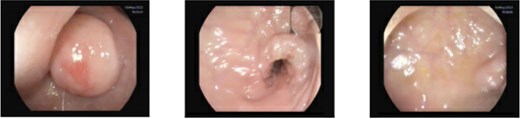

CT scan and colonoscopy revealed a 2-cm submucosal lesion located 23 cm from the anal verge (Fig. 1). Endoscopic ultrasound demonstrated a homogeneously hypoechoic lesion with smooth margins, originating from the muscularis mucosa (Fig. 2). No regional lymphadenopathy was identified. The features were most consistent with a leiomyoma, with gastrointestinal stromal tumour (GIST) considered less likely.

Sigmoidoscopy showing a non-pedunculated subepithelial lesion measuring ≈2.0 cm located 23 cm from the anal verge; the overlying mucosa is intact, the pillow sign is negative, and the lesion does not appear yellowish. The descending colon is normal.